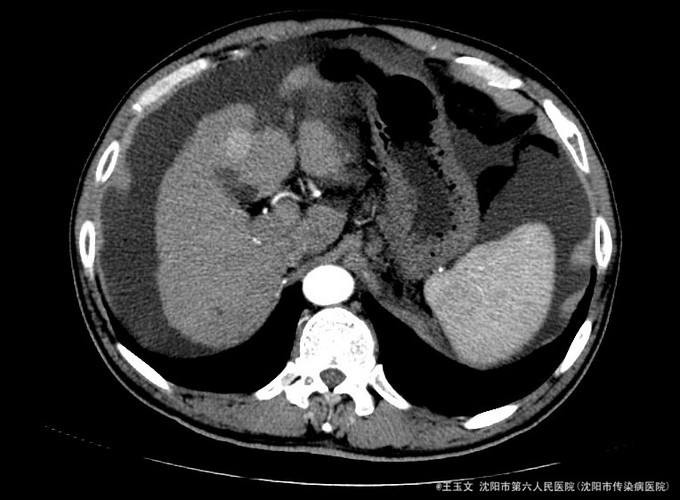

查体:神志清,巩膜无黄染,心肺听诊无异常,腹软,无压痛,肝区无叩痛,移动性浊音阳性,双下肢无浮肿,扑翼样震颤阴性。可见肝掌和腹水等阳性体征 化验结果:天门冬氨酸氨基转移酶 48 U/L、胆碱酯酶 3254 U/L、总蛋白 84.0 g/L、总胆红素 39.9 umol/L、非结合胆红素 26.7 umol/L。凝血酶原时间 15.5 秒、凝血酶原比率 1.35 、凝血酶原百分活动度 54.9 %、活化部分凝血酶原时间 40.7 秒、纤维蛋白原含量 1.255 g/L、D-二聚体 3.05 ug/ml↑。乙型肝炎病毒表面抗原 阳性(+) ↑、乙型肝炎病毒e抗体 阳性(+) ↑、乙型肝炎病毒核心抗体 阳性(+) 。甲胎蛋白(AFP) 11.52 ng/mL。 超声检查示:肝硬化,较多腹水,肝内见多个低回声,较大约1.5*1.0厘米,边界清晰。 肝增强ct:肝脏边缘欠规整,肝裂增宽,各叶大小比例失调,肝实质内见多个低密度结节,较大位于Ⅳ段,大小约2.04cm,增强扫描动脉期Ⅳ段两个结节中等强化,门脉期及延迟扫描呈低密度,余结节无明显强化;肝内亦见多个小囊性密度灶,较大约1.44cm,无强化。肝内外门静脉显示清晰,脾脏增大增厚,超过肝脏下缘,胆囊不大,壁增厚,其内密度均匀,胰腺形态密度无特殊。肝内外胆管未见明显扩张,腹膜后未见明显肿大淋巴结。食管下段胃底贲门区见扩张扭曲的血管影。肝周及腹膜间隙见有中等量液性密度影。

诊断:初步诊断:1、乙肝肝硬化 失代偿期; 确定诊断:乙肝肝硬化 活动性 失代偿期C-P B级 行肝脏增强CT后补充诊断:肝占位性位病变 行DSA下肝动脉造影后修订诊断:原发性肝癌 治疗:限盐饮食,口服利尿剂,减少水钠储留,促进腹水消退,静点异甘草酸镁保肝治疗,行增强CT检查,发现肝内占位,考虑恶性可能大,患者肝功改善后,于局麻下DSA下行肝动脉造影及TACE治疗

术后患者未见TACE治疗并发症,无不适,复查化验结果:天门冬氨酸氨基转移酶 41 U/L、胆碱酯酶 1901 U/L、白蛋白 29.3 g/L、总胆红素 24.6 umol/L。甲胎蛋白测定:甲胎蛋白(AFP) 7.75 ng/mL。患者肝功改善,术后一周时候复查CT示病灶碘油沉积尚好,办理出院。 本例患者比较典型,虽然其术前甲胎蛋白不高,但其增强CT有典型的“快进快出”特征,并且乙肝背景,有经验的医师会考虑其为原发性肝癌的可能非常大, TACE治疗即可以确诊其肝癌,又能在确诊的同时给予治疗。